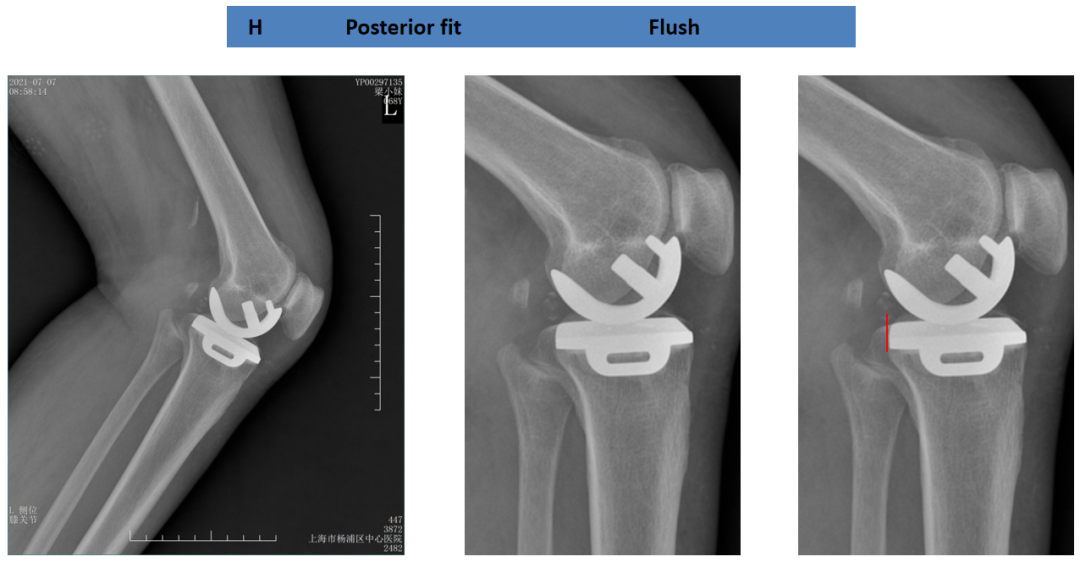

胫骨平台前后覆盖(矢状位)

胫骨假体完全覆盖胫骨截骨面:后缘齐平,假体完全覆盖胫骨平台。

胫骨假体完全覆盖胫骨截骨面:前缘齐平,假体完全覆盖胫骨平台。

胫骨假体完全覆盖胫骨截骨面:假体完全覆盖胫骨平台,与侧壁无间隙。

胫骨平台后缘覆盖不足

胫骨假体对胫骨截骨面的前后覆盖:未完全覆盖胫骨平台,前缘齐平,后缘短2mm。